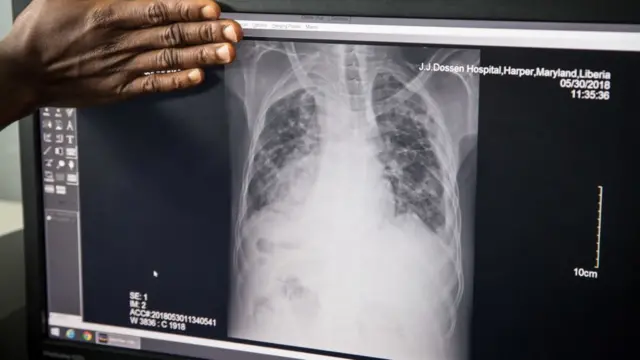

Generalmente ataca los pulmones (aunque también puede afectar glándulas, huesos y el sistema nervioso) y se propaga cuando alguien con la infección estornuda, tose o escupe y otros inhalan las gotitas infectadas que flotan en el aire.

Las bacterias se incrustan en lo más profundo de los pulmones donde se amontonan y atrincheran en nódulos. Para descomponer esos nódulos y atacar las bacterias se requieren meses de, algunas veces, insoportables tratamientos con un sinnúmero de fármacos.